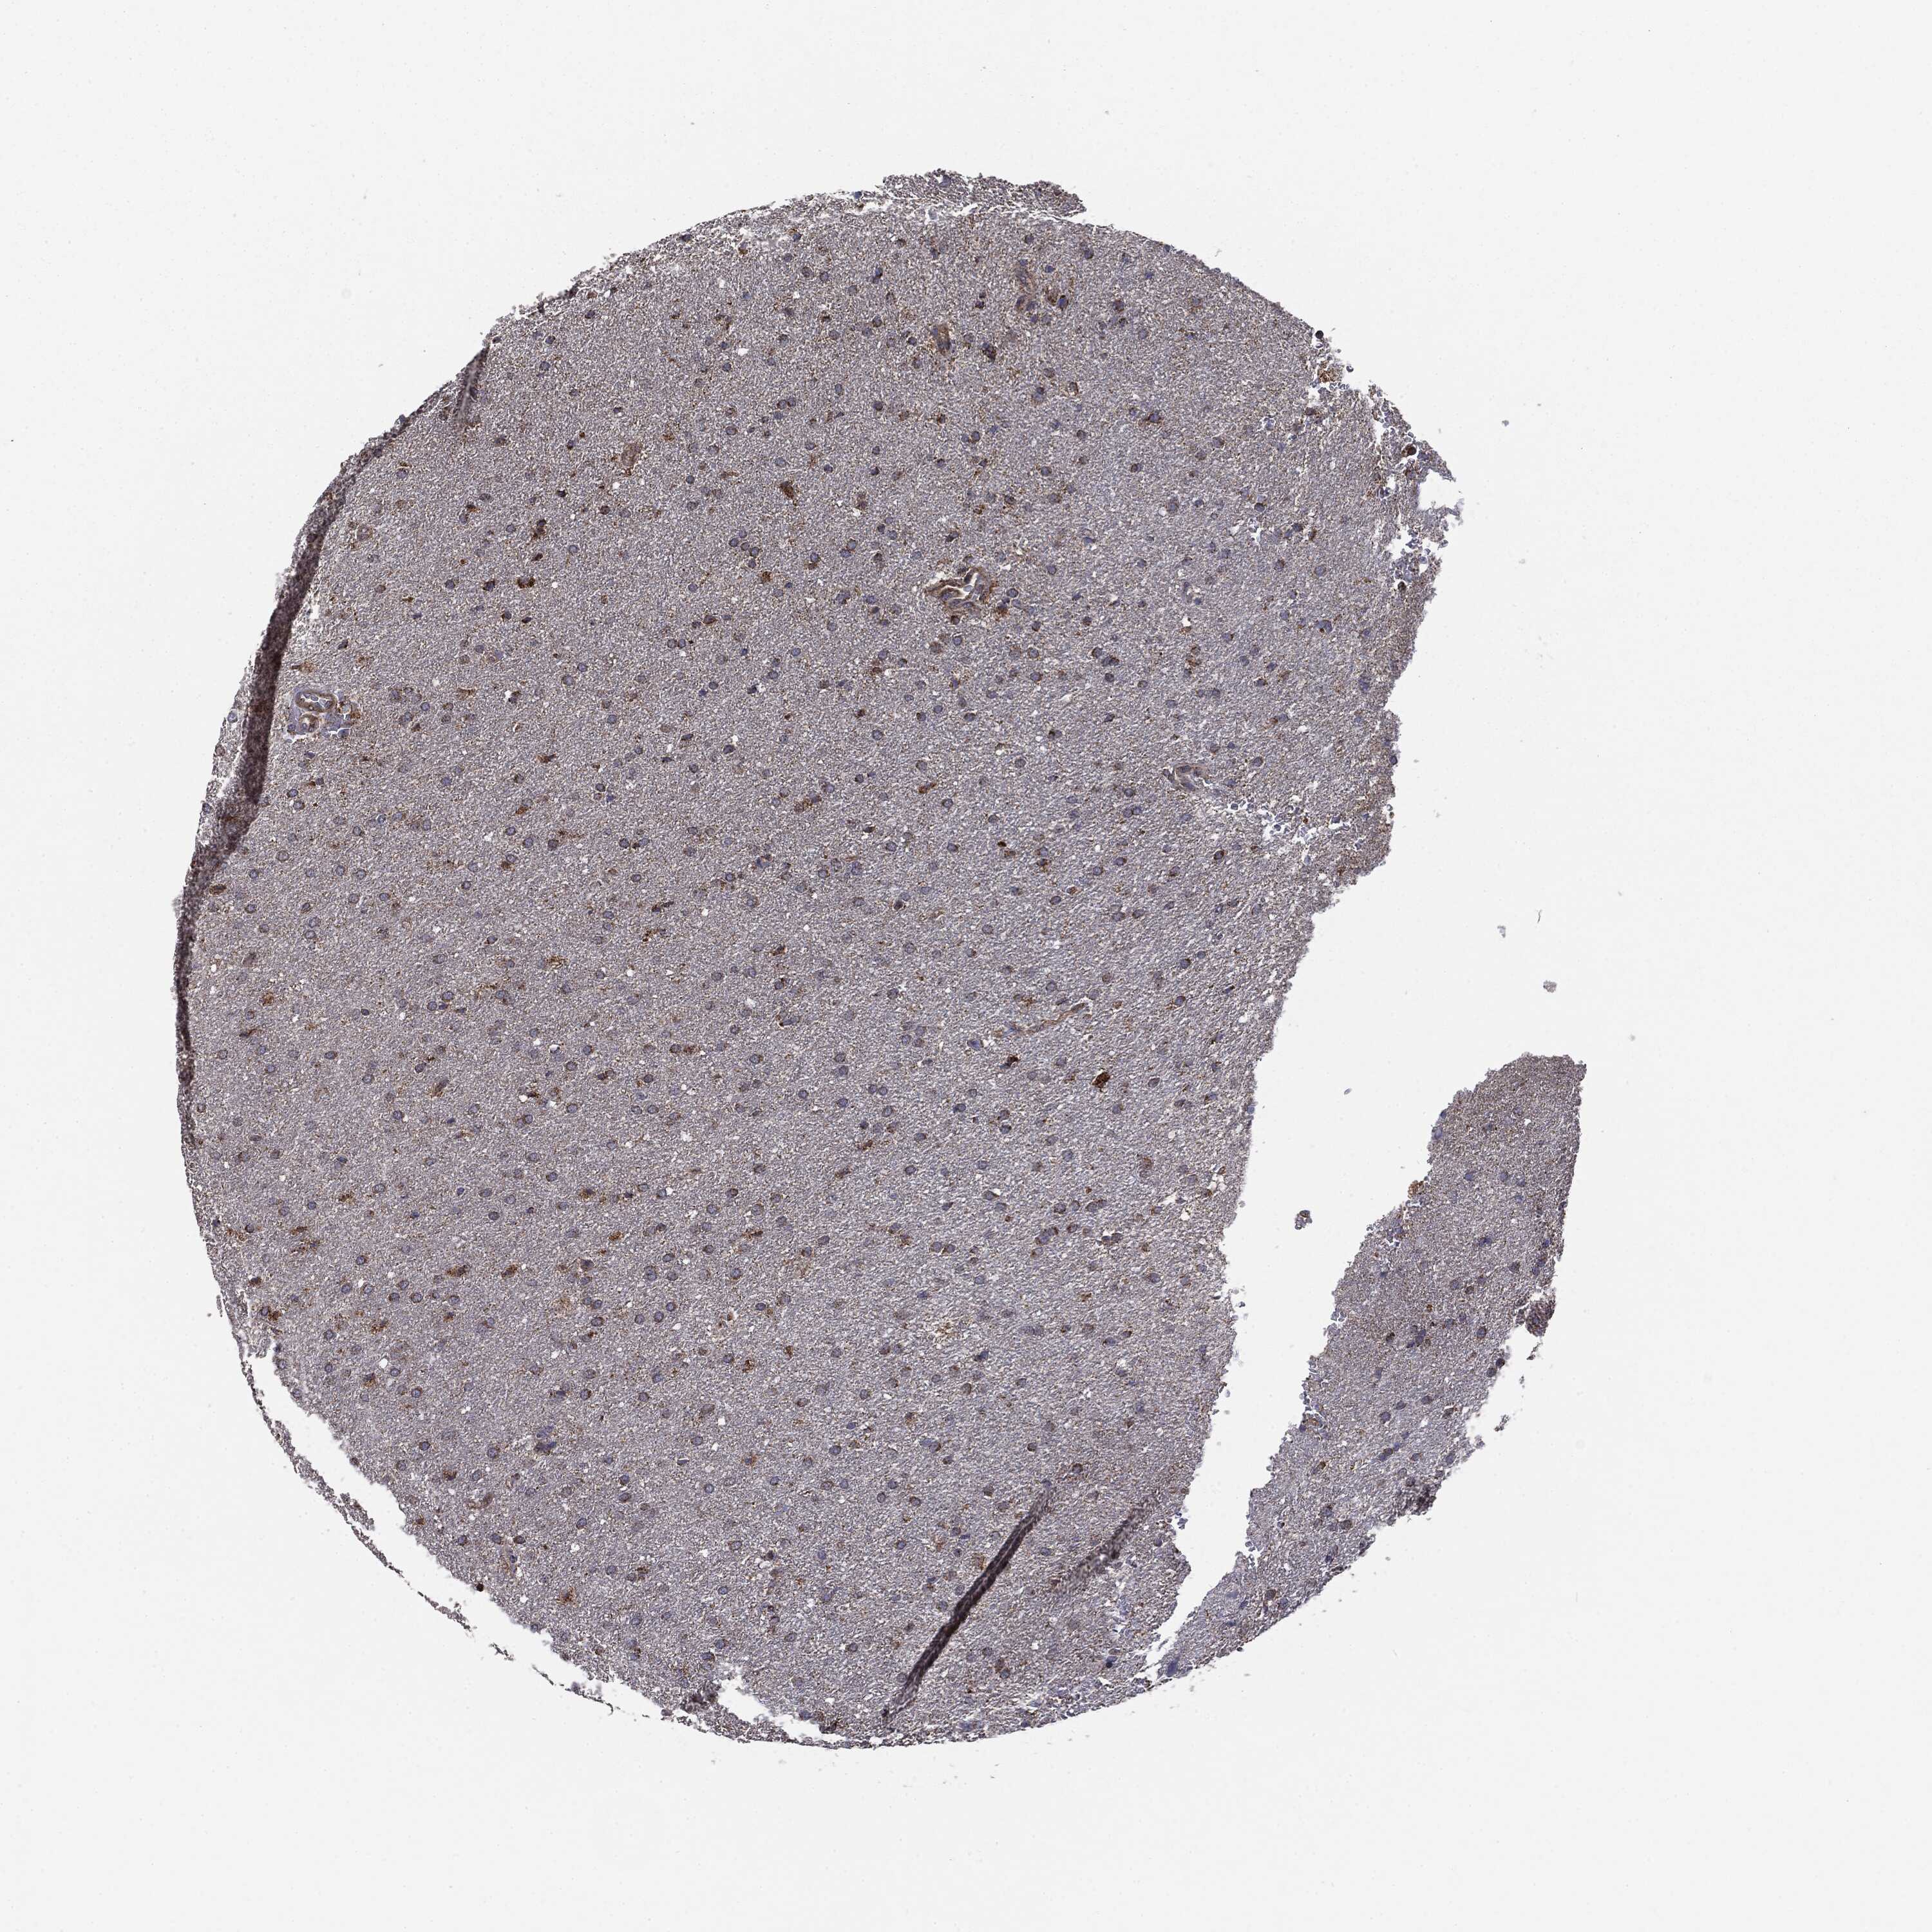

GLIOMA - Protein expressioni

A mouse-over function shows sample information and annotation data. Click on an image to view it in a full screen mode. Samples can be filtered based on level of antibody staining by selecting one or several of the following categories: high, medium, low and not detected. The assay and annotation is described here.

Note that samples used for immunohistochemistry by the Human Protein Atlas do not correspond to samples in the TCGA dataset.

Antibody stainingi

Antibody staining in the annotated cell types in the current human tissue is reported as not detected, low, medium, or high, based on conventional immunohistochemistry profiling in selected tissues. This score is based on the combination of the staining intensity and fraction of stained cells.

Each image is clickable and will lead to virtual microscopy that enables deeper exploration of all samples and also displays staining intensity scores, fraction scores and subcellular localization as well as patient and tissue information for each sample.

CAB069425

CAB080053

CAB080065

CAB080070

CAB080081

CAB080095

CAB080097

Staining

High

Medium

Low

Not detected

Intensity

Strong

Moderate

Weak

Negative

Quantity

>75%

75%-25%

<25%

None

Location

Nuclear

Cytoplasmic/membranous

Cytoplasmic/membranous,nuclear

Glioma, malignant, Low grade

Glioma, malignant, High grade

Glioma, malignant, NOS